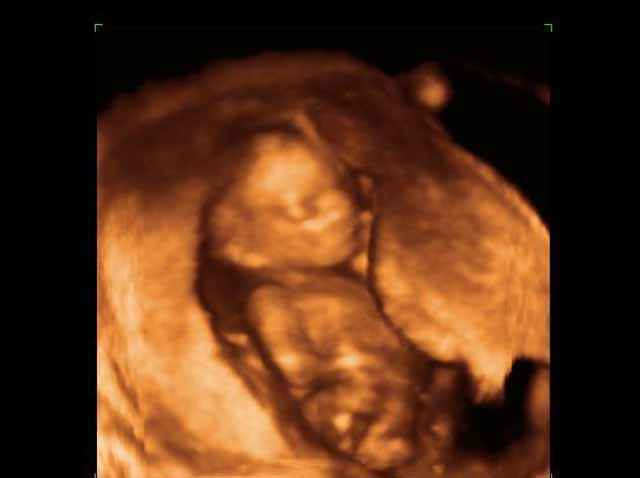

- 3D Fetal Profile Ultrasound Scan Photos

- Fetal Behavior Ultrasound Photos

- Second Trimester Ultrasound Photos

- The Clinical Advantages of 3D and 4D Ultrasound

- Definition and Features of Four Dimensional Ultrasound

- Uses of 4D Ultrasound scan

- The importance of 4D ultrasound imaging in pregnancy